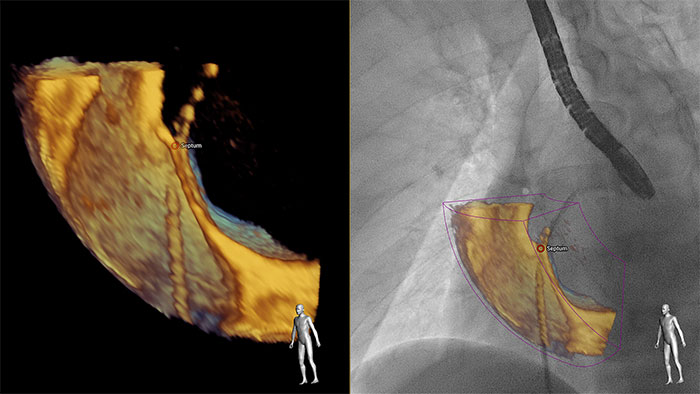

理解を深めるために インターベンション手技中に組織構造、カテーテル、デバイスの位置を確実に把握するため、EPIQ CVx Transcend はマルチモダリティによる意思決定をサポートします。3D 経食道エコーイメージ中に任意にマーカーを置くと、3 次元位置情報を反映したうえで X 線透視イメージ上に反映されます。これにより、インテグレートされた画像を用いて術者同士のコミュニケーションを円滑に図ることができます。

インターベンションとのコラボレーション用に開発されたフォトリアリスティックレンダリング 循環器用 TrueVue は、仮想光源を使用してデバイスの視認性を向上させる、新しい 3D 超音波表示方法です。TrueVue は、組織の詳細と奥行き方向の情報を分かりやすく示す画像を提供して、カテーテルおよびデバイスの位置の把握を容易にします。エコー画像がより分かりやすく表示されることで、インターベンション医は確信を持って処置を行うことができます。新型 EPIQ CVx Transcend を見た臨床医の 90%⁵が、新しい TrueVue 3D フォトリアリスティックレンダリングにより組織構造の表示が改善されるため、臨床的確信を強く持つことができると回答しました²。